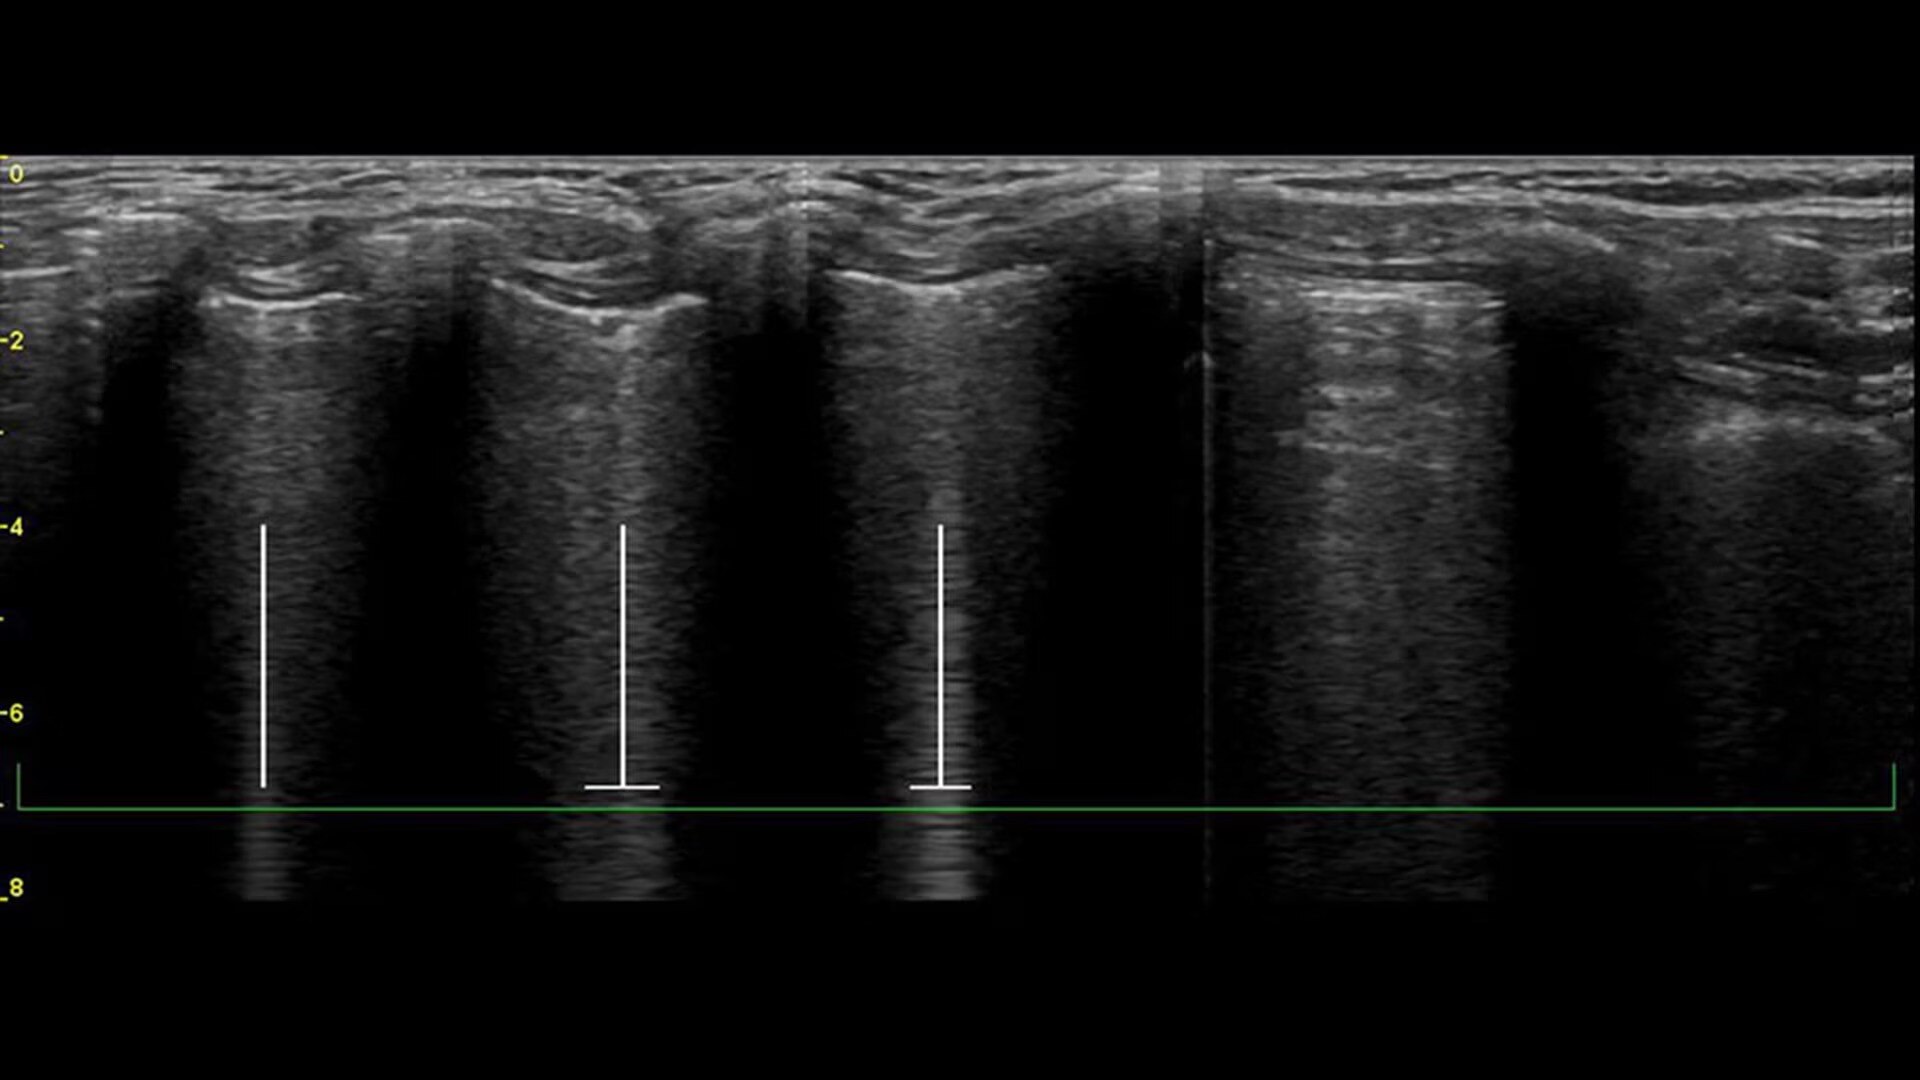

Catheter to Vessel Ratio

Accurate catheter selection tool

Selecting the wrong sized catheter can lead to catheter related thrombosis.2 Catheter to Vessel Ratio is a measurement tool that supports clinicians in selecting the appropriate sized catheter based on vessel diameter.